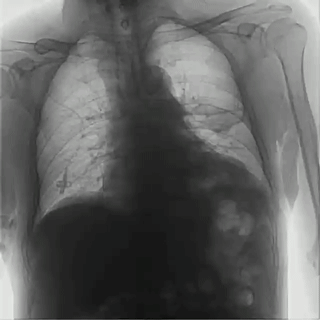

不同于常規(guī)DR只能進(jìn)行平片攝影檢查,普利德多功能動態(tài)平板DRF動靜兼?zhèn)?,可?shí)現(xiàn)大幅面低劑量透視檢查,在日常的體檢工作中,比如胸部及肺部檢查,可對重疊部位病變進(jìn)行可視化觀察及多角度旋轉(zhuǎn)體位,發(fā)現(xiàn)疑似病灶可瞬時完成高清點(diǎn)片,顯著提高診斷的準(zhǔn)確性。

動態(tài)采集幀率最高可達(dá)30幀/s,影像細(xì)膩流暢,便于醫(yī)生對細(xì)微病變的觀察。17×17英寸大幅面成像,在透視過程中能對患者的胸部腹部等部位實(shí)現(xiàn)大范圍覆蓋,便于從整體上觀察組織信息,更加全面且精準(zhǔn)的捕捉病灶。